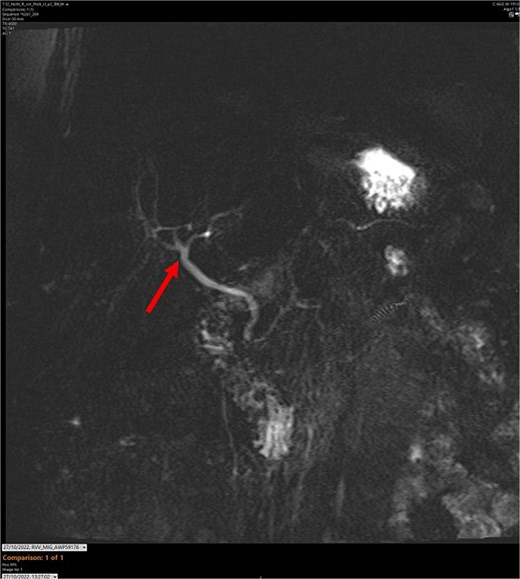

Series of HIDA scans. The arrow points to likely a gallbladder bud.